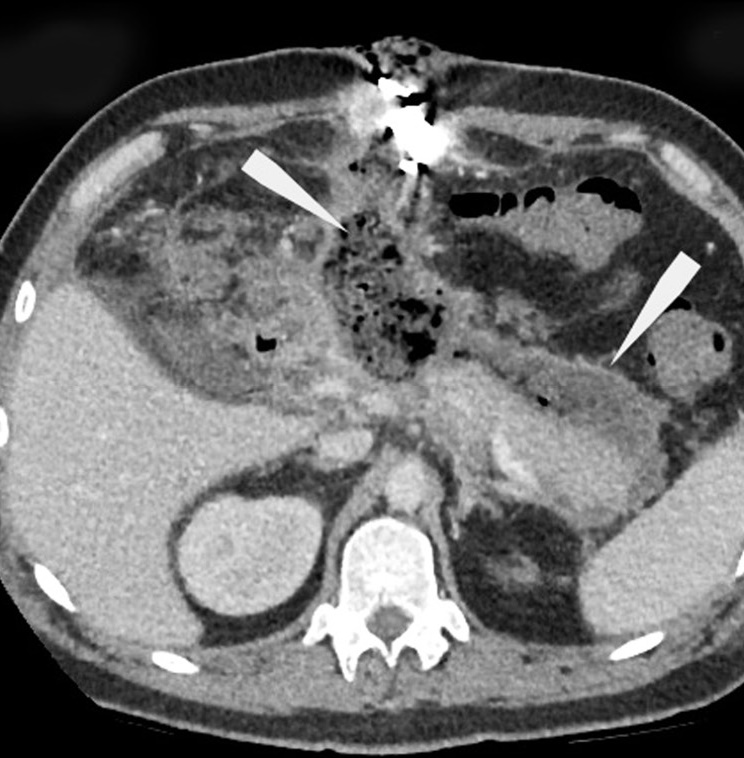

Encapsulated necrotic pancreatitis

Resumo

This study presents a rare clinical case of encapsulated necrotic pancreatitis, which was a complication of acute pancreatitis that arose against the background of alimentary disorders. The aspects of the semiotics of radiation diagnostic methods in the follow-up control of these pathologies were presented.

This case is notable for the manifestation of diseases upon hospital admission, as in the classical edematous form of acute pancreatitis, with a further increase in negative dynamics. This demonstrated the possible stepwise disease development, accompanied by a series of follow-up computed tomography between the clinical and morphological phases of acute pancreatitis and before the formation of pancreatic necrosis, which was complicated by sequestration of the pancreatic body with peripancreatic abscess formation. Afterward, the therapeutic paradigm was changed, and the place of the conservative approach was taken by active surgical tactics, followed by repeated manipulations and follow-up computed tomography and magnetic resonance until the improvement of the patient’s condition.

471-480